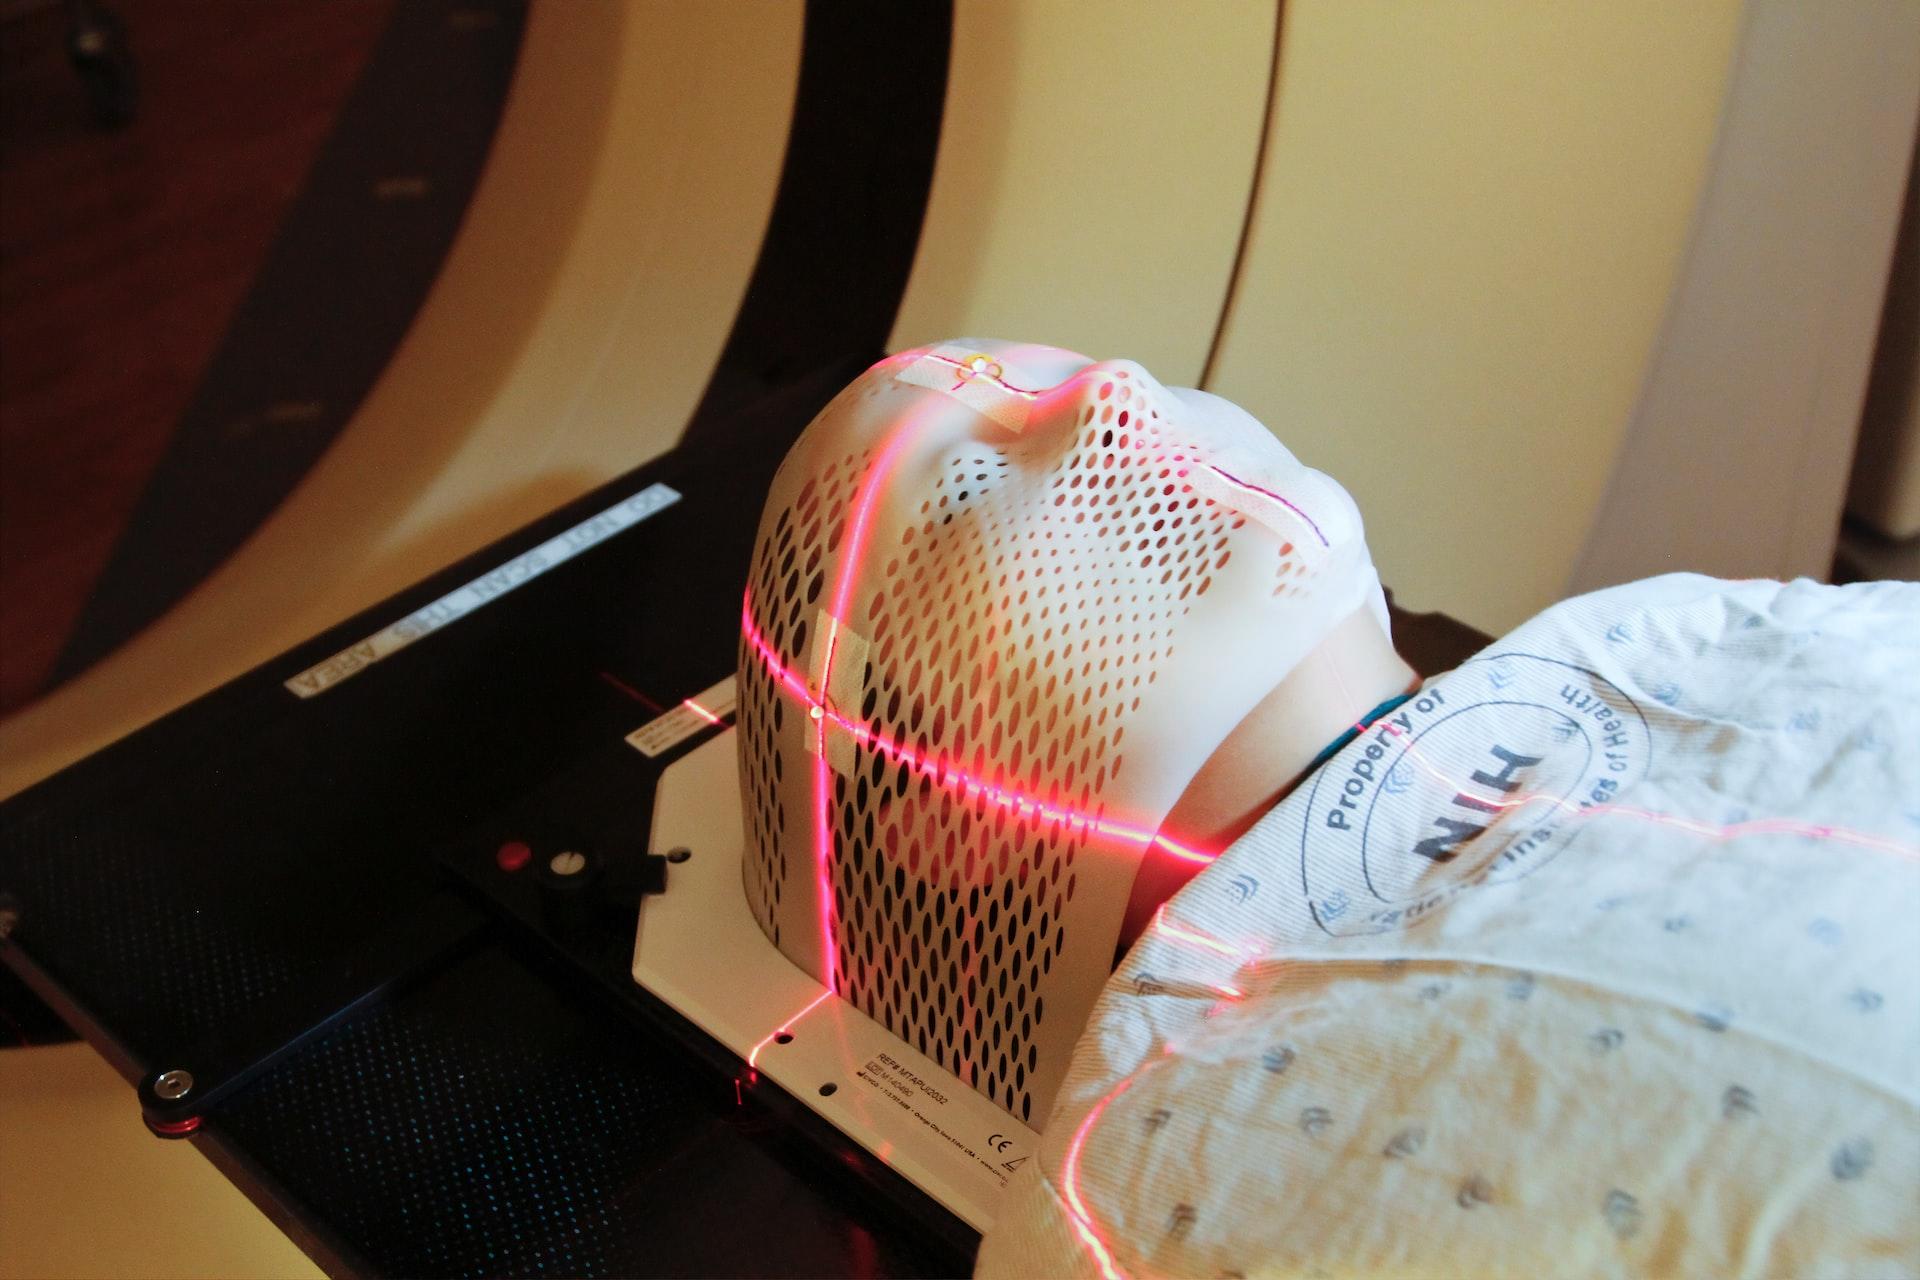

The field also covers the crossroads where physics meets biology in terms of experimental techniques and approaches. Many different imaging techniques are possible thanks to physics, allowing biophysicists to understand better the systems mentioned earlier.

Biophysics also extends into medicine. This is sometimes called medical physics, but applying physics to healthcare, which is arguably a branch of biology, too, is very common, especially when it comes to imaging, radiology, and nanomedicine. Generally, however, biophysics looks to understand how it all works whereas medical physics looks for practical solutions to apply to the human body.